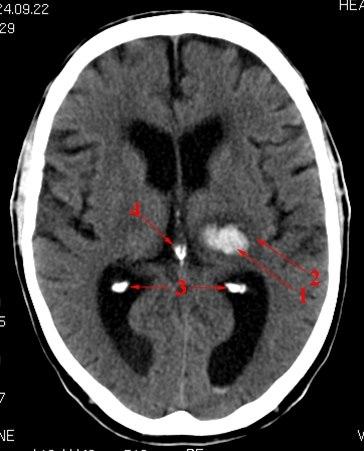

CT axialbilde uten kontrast

Liten blødning (lyst område) i thalamusregionen på pasientens venstre side.

Dessuten ses forkalkninger i plexus choroideus bilateralt og i corpus pineale (intenst hvite områder)

- Blødning i thalamus

- Ødemsone

- Forkalkninger i plexus choroideus

- Forkalkning i corpus pineale